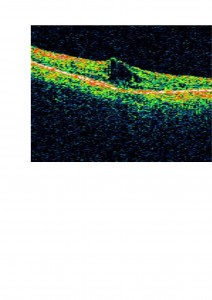

Os presentamos el caso de un paciente atendido en nuestra clínica. Presentaba una aguudeza visual OD 0,3 y OI 0,1 , con cataratas en ambos ojos (mostrada en la foto anterior). En el fondo de ojo presentaba buena coloración de las papilas y en la OCT un edema macular cistoide como os mostramos.

En este paciente decidimos tratar el edema macular cistoide previo a la cirugía de cataratas con acetazolamida oral debido a que muy probablemente iba a empeorar tras la cirugía. En la OCT os mostramos cómo disminuyó el edema: